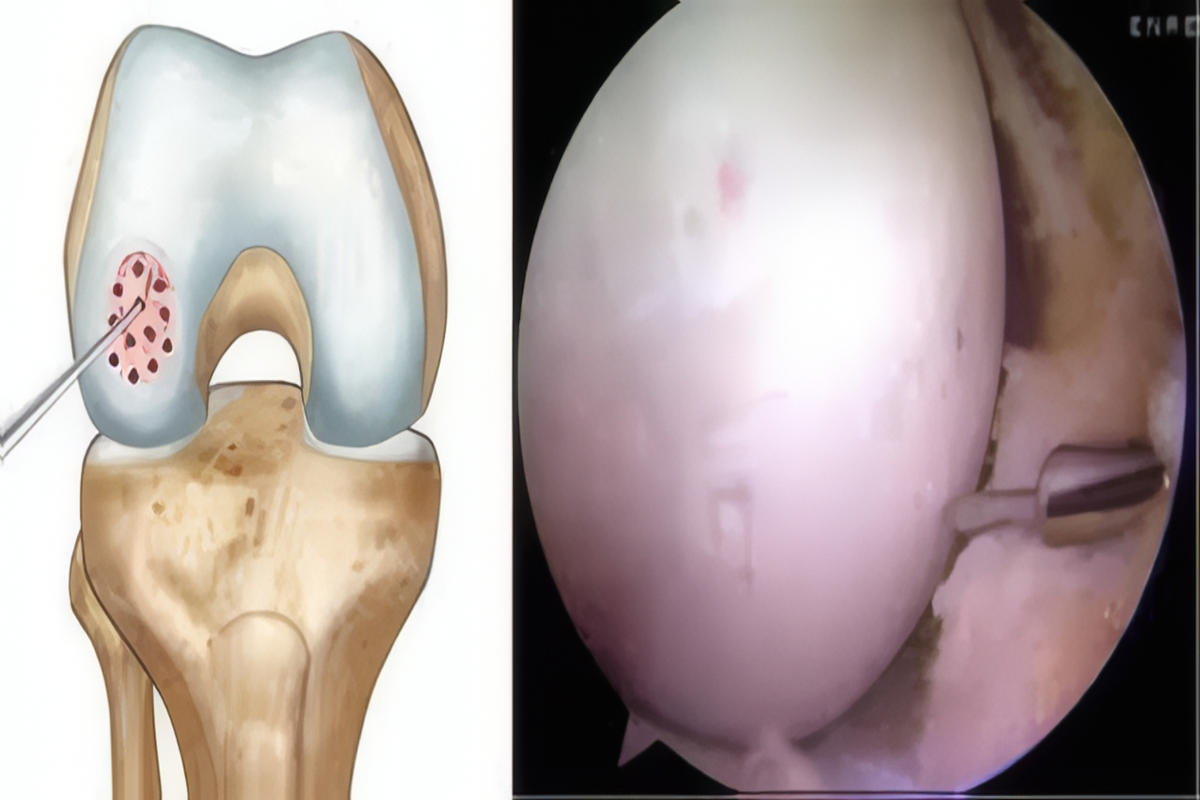

Σε επιλεγμένες περιπτώσεις, η διαγνωστική αρθροσκόπηση προσφέρει άμεση και αξιόπιστη εκτίμηση της κατάστασης του αρθρικού χόνδρου.

Σε εκτεταμένες ή συμπτωματικές βλάβες ενδείκνυται χειρουργική αντιμετώπιση. Οι σύγχρονες τεχνικές περιλαμβάνουν αρθροσκοπικό καθαρισμό και λείανση της βλάβης, μικροκατάγματα που διεγείρουν τον σχηματισμό ινοχόνδρου, αυτόλογη μεταμόσχευση χονδροκυττάρων και μεταμοσχεύσεις οστεοχόνδρινων κυλίνδρων. Σε περιπτώσεις εκτεταμένης φθοράς μπορεί να εξεταστεί και η λύση της μερικής ή ολικής αρθροπλαστικής γόνατος.